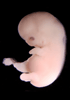

Carnegie Stage 20 (50 post-ovulatory days)

Most embryos at stage 20 are approximately 50-51 postovulatory days old and measure 21-23 mm in length. Distinguishing criteria for this stage include upper limbs slightly bent at the elbows, short stubby fingers, hands curving over the cardiac region but still far apart from each other, and a fringe-like vascular plexus that marks growth centers laterally in the superficial tissues of the head.

Although some of the photographs below show abnormal embryos, the animations and MRI slice images all depict normal embryos. Abnormal embryos are noted in the titles of the large photos when they are opened.